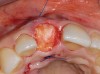

A 59-year-old woman presented with a recent history of trauma to her pre-maxilla, resulting in vertical root fracture of the maxillary left central incisor (Figure 1 and Figure 2). Examination revealed a mobile crown, moderate flat periodontal biotype, gingival margin of the left central incisor 1 mm coronal to that of the adjacent central incisor, central incisor tooth width discrepancy, and a medium smile line. The treatment plan included flapless extraction of the fractured tooth with the potential for simultaneous socket grafting using mineralized bone allograft (MinerOss®, BioHorizons, Inc, Birmingham, AL) and a free gingival graft (Figure 3) harvested from the left palate. Post-extraction examination revealed vertical labial plate loss of 2 mm and class I interproximal height of bone; therefore, all three procedures were performed. Four months postsurgery (Figure 4), a mid-crestal and sulcular incision without release was made to allow for crestal plasty and core biopsy (Figure 5). Histomorphometry revealed 87% vital bone with minimal evidence of residual allograft (Figure 6). This finding was consistent with type II bone density and allowed for non-submerged implant placement. The labial plate was completely regenerated. A provisional crown was placed and contoured to groom the soft tissue for 3 months (Figure 7), followed by final crown fabrication (Figure 8).

Figure 3  Completed socket graft with free gingival palatal graft.

Figure 3